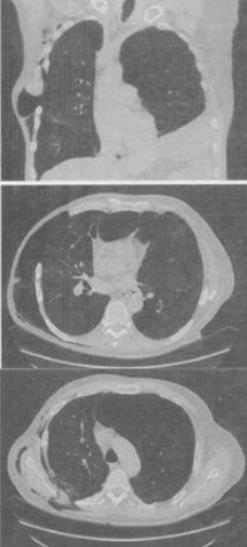

- 单项选择题 患者男,68岁,胸闷,气逼1年余,加重1周,右胸有手术史,结合CT图像,最可能的诊断是()。

A、右侧气胸并皮下气肿、左侧肺气肿

B、右侧气胸并皮下气肿、左侧肺不张

C、双侧肺气肿

D、右侧气胸并皮下气肿

E、右侧肺间质病变、左侧肺气肿

- A